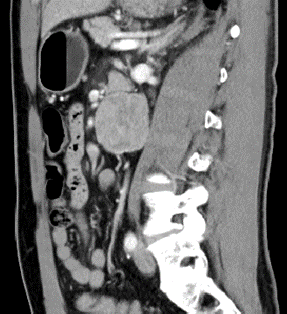

l CT:腹膜后腹主动脉旁软组织密度肿块,边界清,约4.2*4.3cm,密度不均,增强扫描皮髓质不均匀强化,实质期强化稍低,排泌期进一步减低。左肾2.0*2.3cm囊状低密度影。结论:左侧腹膜后占位,副神经节瘤?,左肾囊肿

6、 肾门下方、输尿管内侧和腹主动脉旁探及本次腹膜后肿物,目测尺寸5*5.5cm。复习CT可见肿瘤与腹主动脉关系密切,明显增强提示其血供丰富。术前阅片发现,肠系膜上动脉主干因肿瘤推挤向左侧移位。完整剥离减少出血是本次手术的重难点。且周围靠近十二指肠,操作中注意保护。

本例诊断为副神经节瘤,其与肾上腺内嗜铬细胞瘤同来源于神经节组织,位于交感神经旁,腹膜后主动脉和下腔静脉旁较多见。副神经节瘤为功能性神经内分泌肿瘤,好发于30~50岁,占腹膜后肿瘤的1%~3%,多位于肾动脉至腹主动脉分叉水平的主动脉旁区域。副神经节瘤为富血供肿瘤,增强后明显强化,动脉期显著,可有多支血管同时供应,肿块周围或实性成分内可见迂曲增粗的肿瘤血管,提示完整切除肿瘤、同时避免出血为手术团队提出了很大挑战。